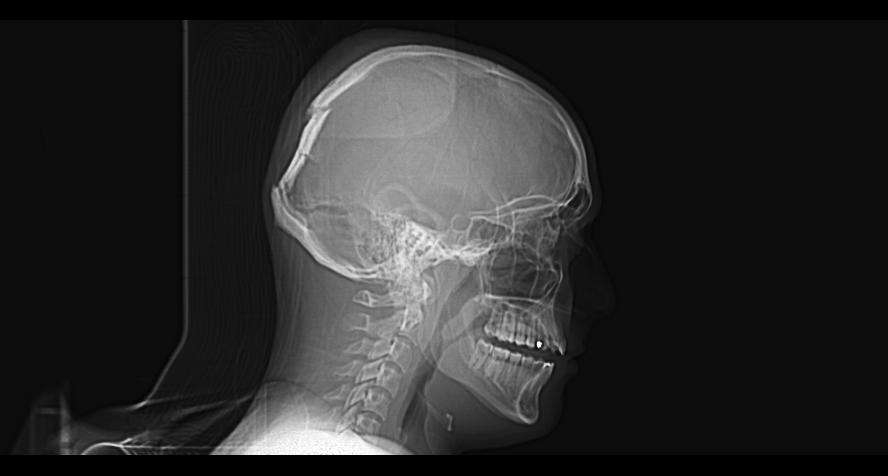

Screenshot20231[...].jpg 414Кб, 2340x1080

2340x1080

Screenshot20231[...].jpg 482Кб, 2340x1080

Боя, я в ахуе, вы в каком веке живёте. Есть такая штука как КЛКТ, стоит копейки, делается 2 минуты. Является золотым стандартном диагностики ЛЮБЫХ зубных пиздецом, там в 3д видно все - кисты, периодонтиты, состояние пазух и тд. Любой приличный врач а) не станет производить серьёзных манипуляций без таких снимков б) спокойно все увидит и распишется где и из за чего у вас болит. Нет бля ходят что-то лечат неизвестно что, не могут определить что и где у них болит, вы ебанутые?